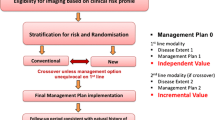

For whole-body (i.e. eyes-to-thighs) or total-body (i.e. head-to-toes) imaging, several bed positions are acquired and merged. Modern PET systems require between 1 and 3 min per bed position, and the amount of bed positions needed is defined by the length of the required scan and the axial size of PET FOV. The latter in the current PET/MR scanners vary between 18 and 25.8 cm with overlap up to 50 % [60, 61]. On the other hand, diagnostic MR protocols may easily surpass 60 min of total acquisition time. The type of acquisition for both subsystems can vary significantly and, on some occasions, the protocols may need modifications in light of new data arising from one of the two modalities. For example, in a staging examination, both local disease and possible distant metastases, need to be assessed. In that case MRAC/localisation scan, followed by the FDG-PET acquisition is performed first and findings may indicate the distant regions with suspected metastasis to be interrogated later on by the localised diagnostic MR contrasts (e.g. in breast cancer staging).

On the other hand, in a different scanner with sequential acquisition capabilities, one option would be to perform all the diagnostic MR acquisitions at the beginning, followed by MRAC dedicated sequences and then PET. A clinical indication which would use such a protocol (Fig. 3.4) is to assess response to treatment or in Head/Neck cancer surgery planning [59]. Workflow optimisation is even more necessary for sequential acquisition settings, since the luxury of PET acquisition during MR is not present. Hence, current sequential scanner designs are trying to leverage technologies from both modalities such as Time-of-Flight (TOF) PET and multiple transmission MRI in order to minimise the required imaging time. The MRAC whole-body scan requires approximately 4–6 min [69], while a TOF PET scan is shown to be performed as fast as 30s/bed position [70, 71] but times between 1-2 min/bed are more common. The decision for how long to acquire PET data depends on the site preferences and experience with TOF-PET systems. Examples in literature exist which demonstrate the use of PET with short acquisition protocols for FDG [72] and other radio-tracers [73].

Generalised simultaneous (top) and sequential (bottom) PET/MR whole-body imaging protocols. Diag-MR and MRAC indicate diagnostic MR acquisitions and MR sequences for attenuation correction and PET localisation, respectively. Solid bars indicate the minimum required acquisitions while hatched bars are extra imaging required by specific imaging protocols and their relative positions. The two time axes do not suggest equal acquisition time between the two protocols